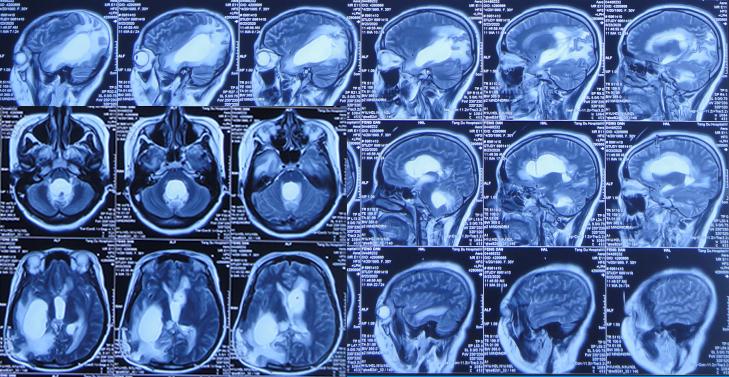

2020年6月21日(开颅术后80天),病情变重:言语变少,左侧肢体活动变差且无法下地行走,查头颅MRI示脑积水脑膨出变更严重( 图-9 )。

图-9: 2020年6月21日头颅MRI

2020年6月23日(开颅术后82天),上午10点左右,出现意识变差,频繁头痛呕吐,急诊第2次转回第二家医院省级某三甲医院,查头颅MRI( 图-10 ),后急诊进行了左侧脑室外引流术。

图-10: 2020年6月23日头颅MRI